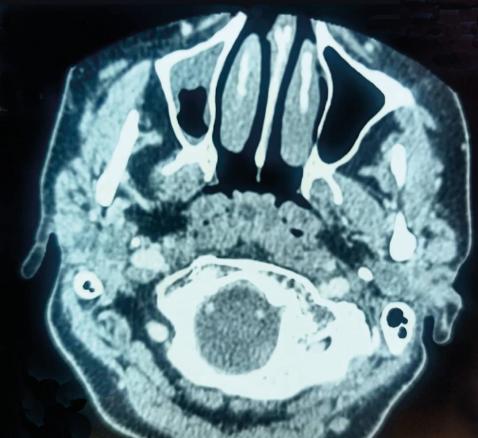

Une patiente âgée de 40 ans est admise à l’hôpital pour exploration d’adénopathies cervicales. L’interrogatoire révèle une obstruction nasale chronique accompagnée d’une rhinorrhée. L’endoscopie met en évidence une rhinite croûteuse avec un bombement du cavum (fig. 1). La tomodensitométrie montre un cavum pseudotumoral (fig. 2, 3 et 4). L’histologie objective un processus granulomateux tuberculoïde (fig. 5). Le GeneXpert sur fragment de biopsie, l’intradermoréaction à la tuberculine et la recherche de bacille de Koch dans les crachats sont négatifs.